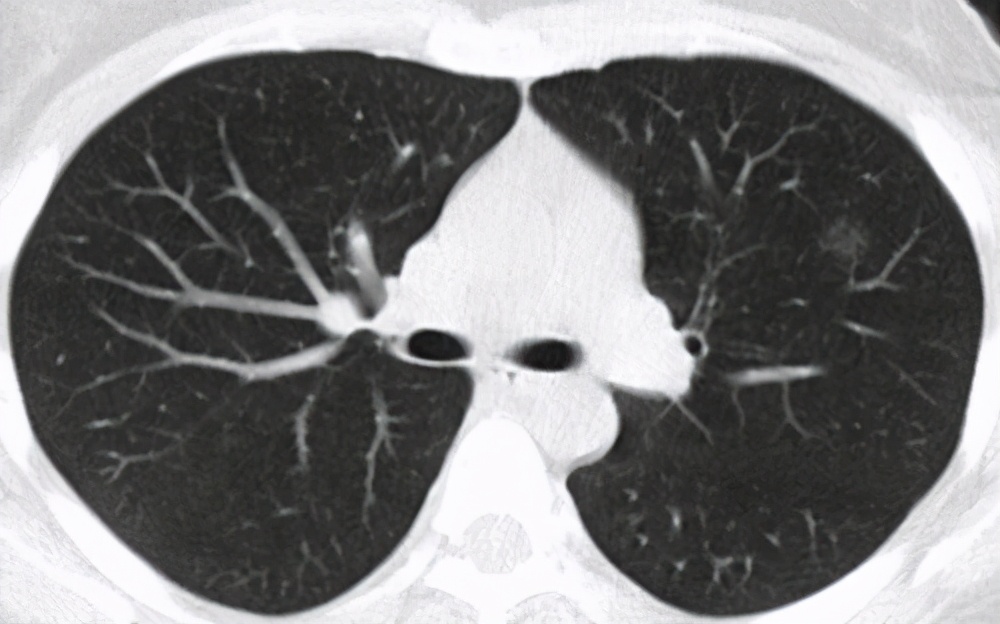

The most obvious manifestations of COVID-19 are fever, fatigue, and dry cough. Additionally, there is a highly distinctive imaging feature: multiple ground-glass opacities and infiltrates in the lungs.

Ground-glass opacities in the lungs are a finding on chest CT scans, typically caused by various inflammations, edema, fibrosis, tumors, etc. They are particularly significant for the early diagnosis of lung cancer.

Due to the impact of this pandemic, many people underwent chest CT scans with the initial intention of screening for the virus. However, this led to the discovery of many early-stage lung cancer cases.

CT is currently the most important method for screening lung cancer. It can detect early-stage lung cancer and display the location and size of lesions. Given the current economic and medical levels, it is a relatively convenient, safe, and economical method for lung cancer screening.